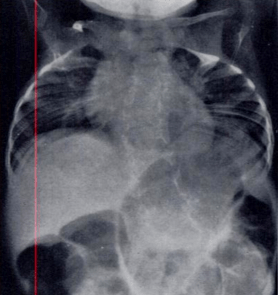

| Radiograph depicting typical skeletal features of Jarcho-Levin syndrome, subtype spondylothoracic dysplasia. Note fanlike configuration of the ribs, with extensive posterior fusion, along with multiple vertebral segmentation defects. | |

Spondylothoracic dysplasia, or STD, has been repeatedly described as an autosomal recessively inherited condition that results in a characteristic fan-like configuration of the ribs with minimal intrinsic rib anomalies. Infants born with this condition typically died early in life due to recurrent respiratory infections and pneumonia due to their restricted thorax.[3][5][18] Recently, a report[13] has documented that actual mortality associated with STD is only about 50%, with many survivors leading healthy, independent lives.

In contrast to STD, the subtype spondylocostal dysostosis, or SCD features intrinsic rib anomalies, in addition to vertebral anomalies. Intrinsic rib anomalies include defects such as birfurcation, broadening and fusion that are not directly related to the vertebral anomalies (such as in STD, where extensive posterior rib fusion occurs due to segmentation defects and extreme shortening of the thoracic vertebral column).[13] In both subtypes, the pulmonary restriction may result in pulmonary hypertension, and have other potential cardiac implications.[19]